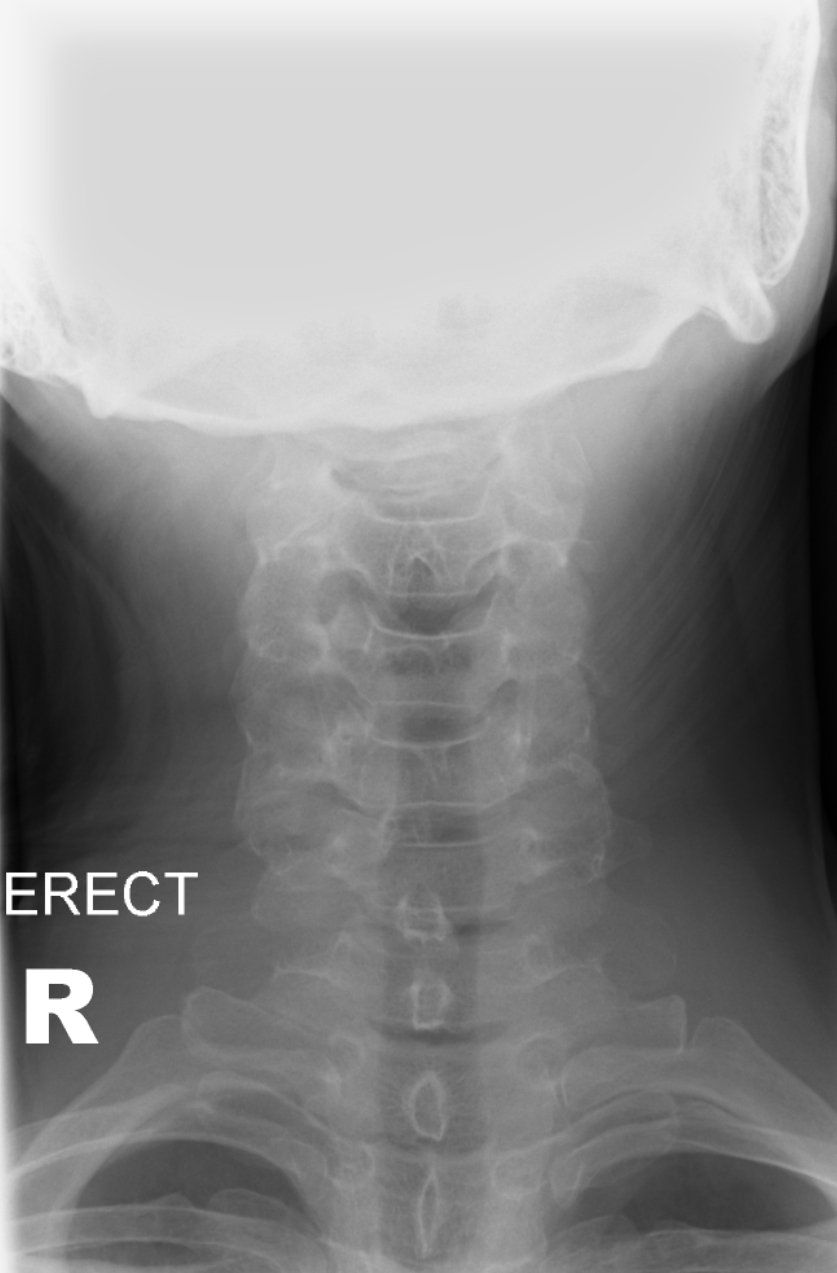

Female. Age 25. Road Traffic Accident (RTA).

Painful neck. Tenderness in the mid cervicle spine. No abnormal neurological findings.

Any evidence of a fracture and/or a subluxation?

RADIOGRAPHS